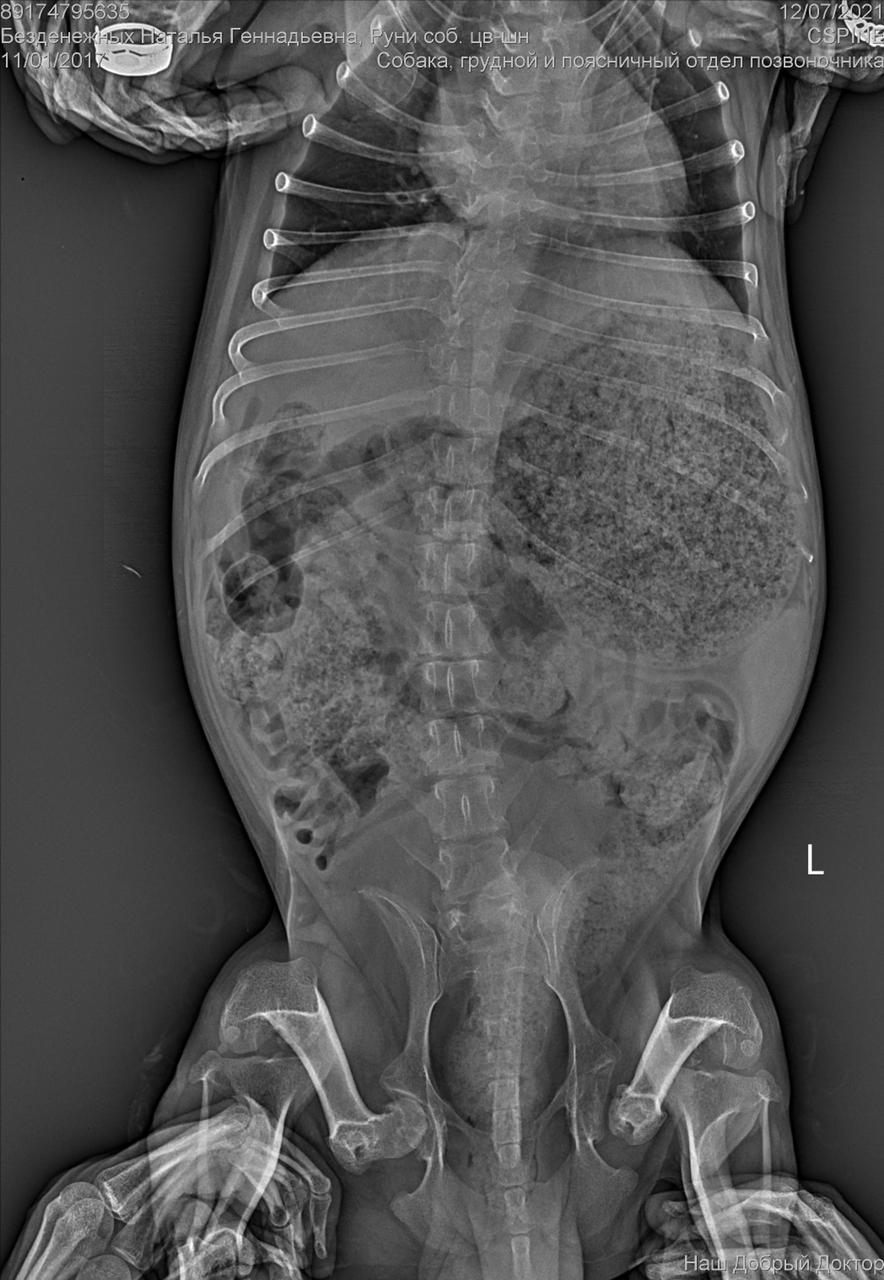

С собакой сегодня поедут в клинику. Передержать и полечить смогут. Попросила в клинике посмотреть клеймо и посканировать ип.

ПОнадобится наша помощь с оплатой лечения и поиском дома.